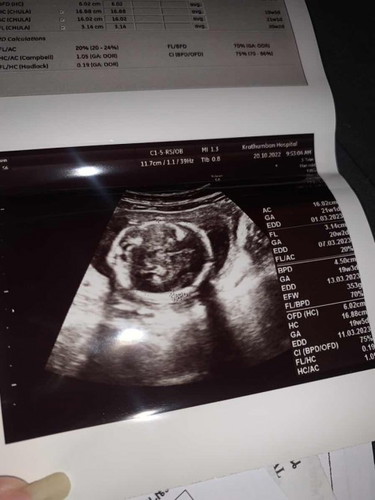

ซาวด์ตอน12w หมอบอกคลอด21 มี.ค. ค่ะ เพศชาย. พึ่งไปซาวด์ล่าสุด เลื่อนมา 17มี.ค. ค่ะ

เปลี่ยนเรื่อยๆจ้า หมออิงจากขนาดตัวน้อง

บ้านนี้หมอบอกผู้หญิง70%จ้าา

ประมาณ 11มีนา ลูกชายครับ 😁ตื่นเต้นๆๆ ลูกคนแรก ดิ้นเก่ง โชว์จู๋ชัดเจน